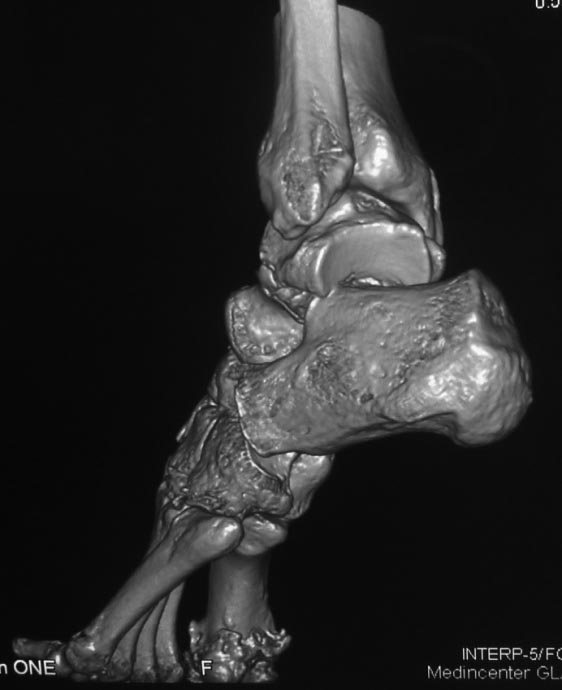

Вероятнее всего, речь изначально шла о не устраненном во время операции

вывихе проксимального фрагмента таранной кости. Во вложении похожий

случай, оперированный 10 дней назад (с послеоперационными снимками). Для

сравнения стрелками на двух рентгенограммах показан нависающий над

пяточной костью вывихнутый фрагмент таранной кости. На компьютерной

томограмме видно гораздо лучше. Так что о живом подтаранном суставе при

сохраняющемся подвывихе говорить не приходится. Кстати, остеотомия

внутренней лодыжки в такой ситуации - нормальный этап доступа, который

должен планироваться до операции, а не быть следствием "тяжелой

репозиции". Сейчас же, судя по плотности проксимального фрагмента, нужно

исключать асептический некроз таранной кости и ее несращение. От этого

будет зависеть тактика. Без КТ не обойтись. Во всяком случае, артродез

голеностопного сустава при несросшейся разрушающейся таранной кости

точно не будет правильным решением.